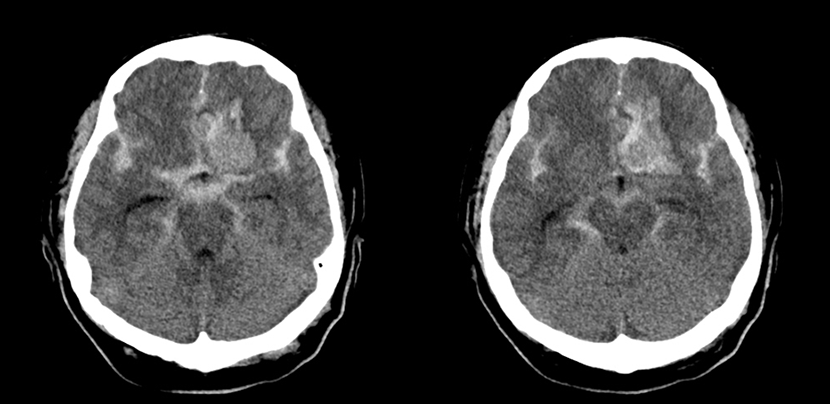

수술전 뇌CT 영상에서 뇌지주막하출혈 소견이 보임